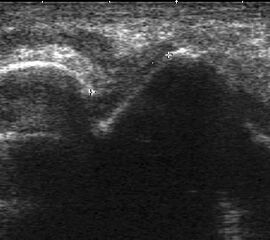

Echogene Verdickung im Subkutangewebe bei Lymphödem

Abbildung 8

Lagerung: Rückenlage.

Schnittebene: Ventraler LS über dem OSG.

Referenzstrukturen: Distale Tibia und Talusrolle, darüber Gelenkkapsel. Befunde: Echogene Verdickung subkutan (Abb. 8), hier peronäal oberhalb des OSG. Bei Varicosis sind in der Subkutis erweiterte Venenkomplexe mit echoarmem Lumen und positivem Doppler-Signal zu sehen.